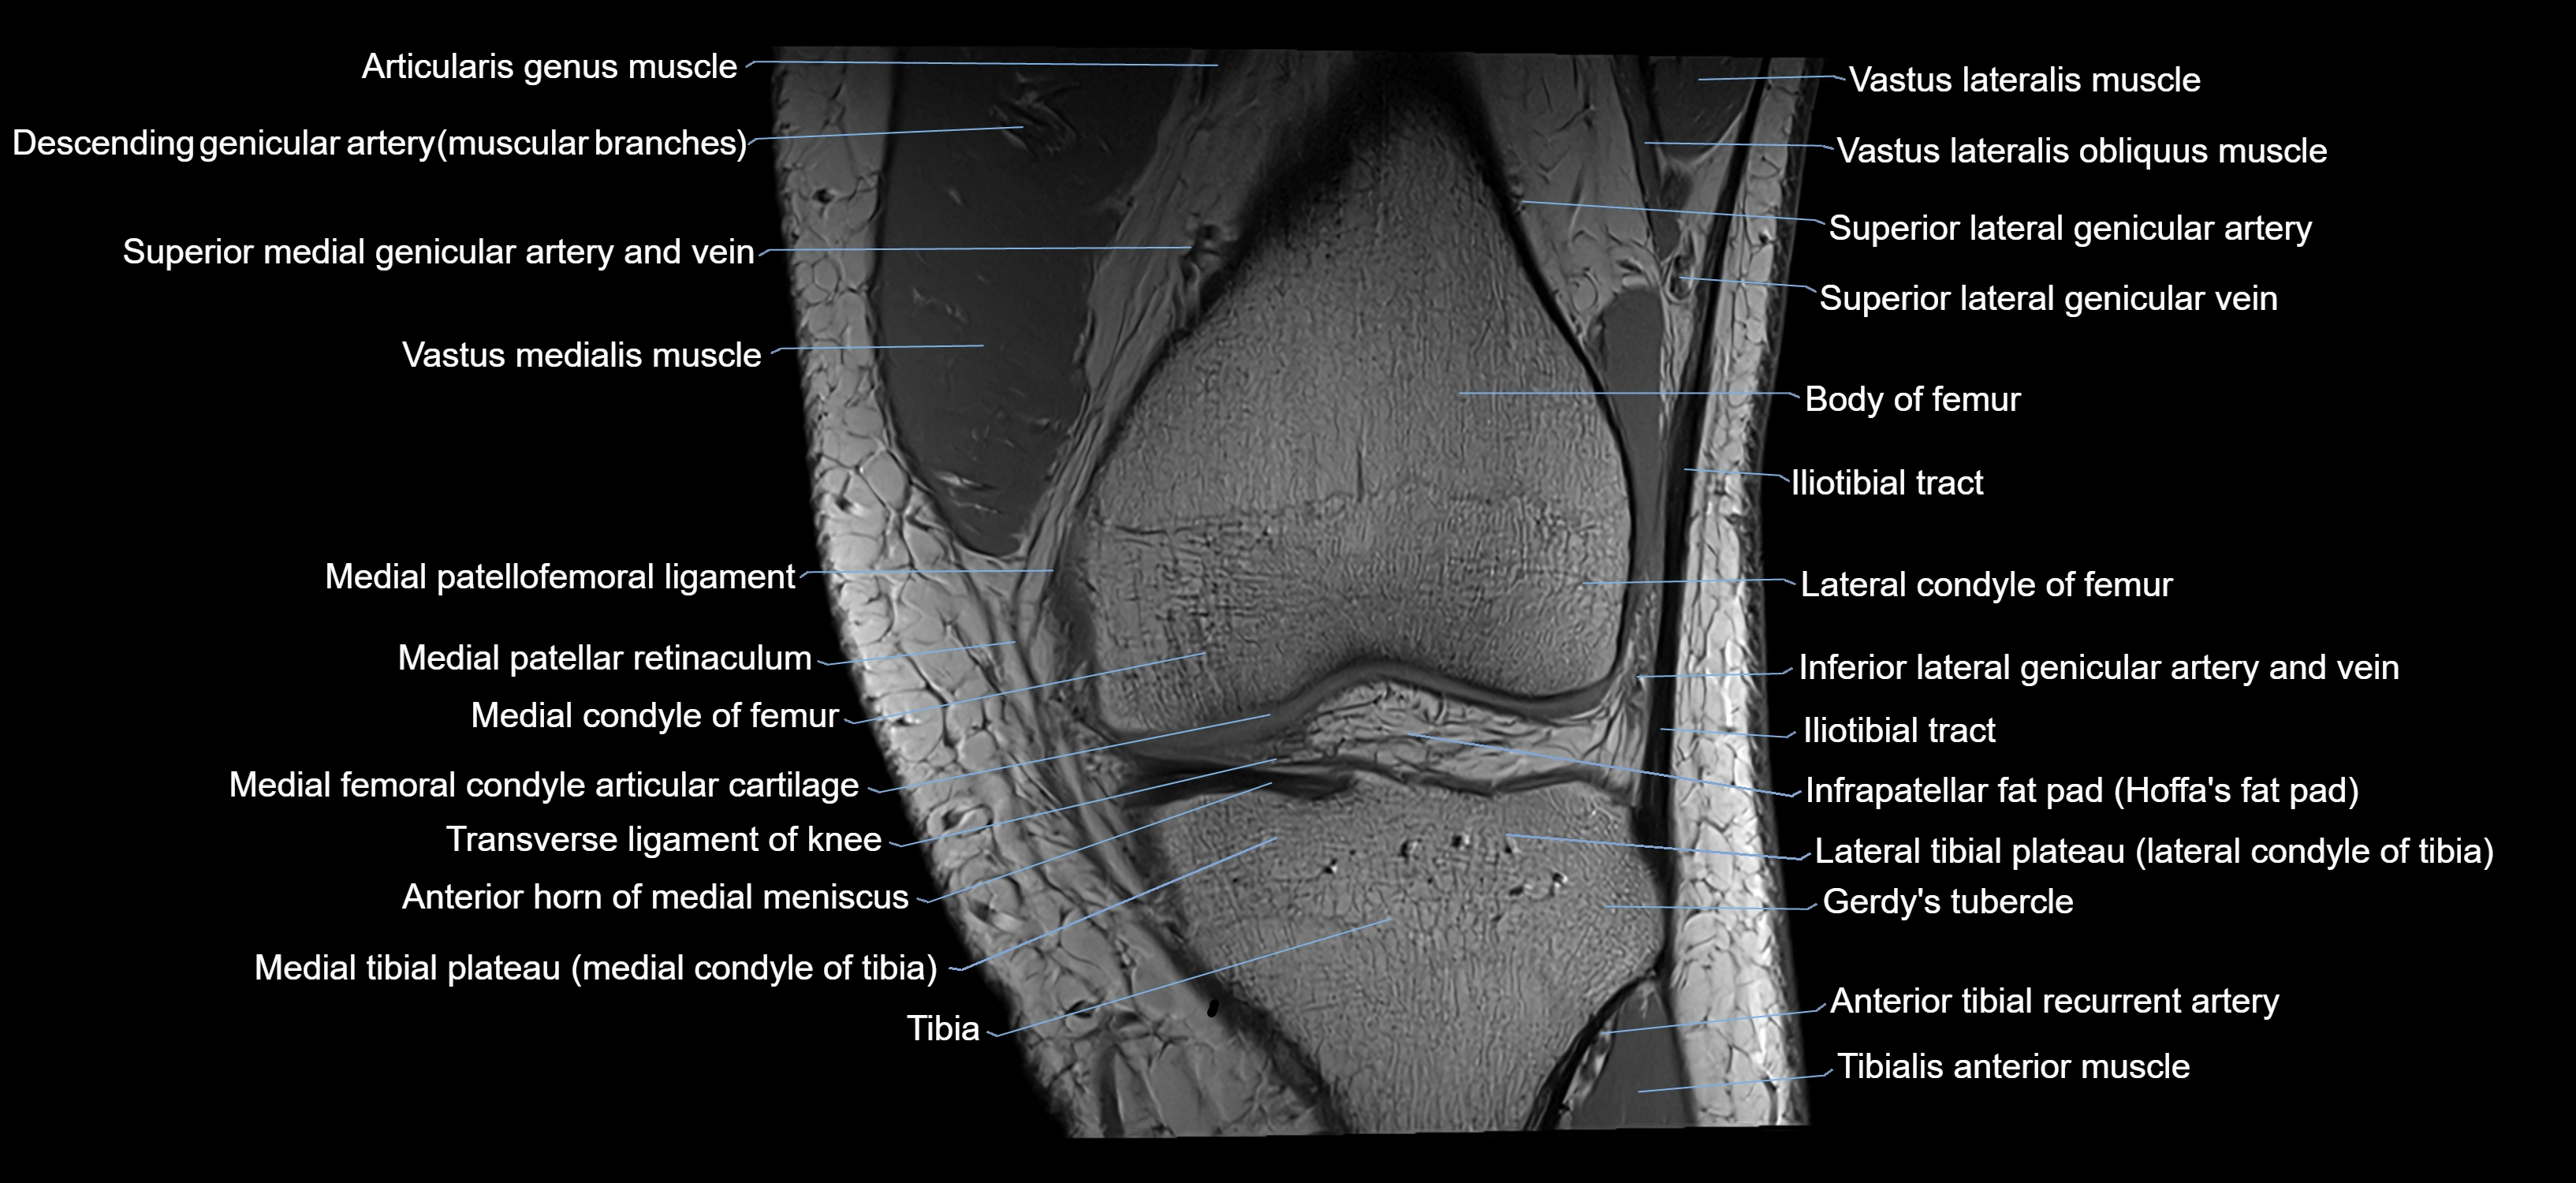

- Anterior horn of medial meniscus

- Femoral condyle articular cartilage

- Gerdy’s tubercle

- Infrapatellar fat pad

- Lateral condyle of femur

- Lateral condyle of tibia

- Lateral tibial plateau

- Medial condyle of femur

- Medial condyle of tibia

- Medial patellar retinaculum

- Medial patellofemoral ligament

- Superior lateral genicular artery

- Superior lateral genicular vein

- Tibialis anterior muscle

- Transverse ligament of knee

- Vastus Lateralis Obliquus Muscle

- Vastus lateralis muscle

- Vastus medialis muscle